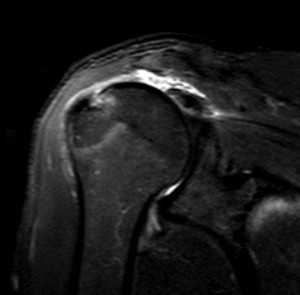

Разрыв вращательной манжеты - также характерное повреждение области плеча - может быть связан как с травмой, так и дегенеративными процессами. Разрывы вращательной манжеты бывают полные и неполные. Кроме того, по МРТ плечевого сустава выделяют 3 градации, в основе которых лежит не только изменение сигнала на Т2-зависимых томограммах, но и морфологические изменения сухожилия.

МРТ. Корональная Т2-зависимая томограмма с подавлением сигнала от жира. Полный разрыв сухожилия надостной мышцы.

МРТ плечевого сустава с подавлением сигнала от жира. Т2-взвешенная корональная МРТ. Перелом большого бугорка (стрелка).

При МРТ плечевого сустава косвенным признаком разрыва вращательной манжеты служит высокий сигнал на Т2-взвешенных от поверхности сустава до субакромиальной (субдельтовидной) сумки. Частичные разрывы чаще всего по передней поверхности сухожилия м.supraspinatus, реже примыкая к большой бугристости или сухожилия м. infraspinatus.

МРТ плечевого сустава. Т2-взвешенная корональная МРТ. Субакромиальное скопление жидкости - косвенный признак разрыва вращательной манжеты.

МРТ плечевого сустава. Т1-взвешенная корональная МРТ. Частичный разрыв вращательной манжеты.

МРТ плечевого сустава. Т2-взвешенная корональная МРТ. Передний разрыв вращательной манжеты